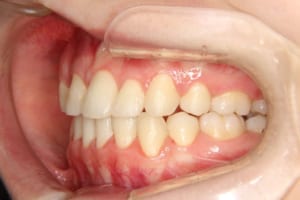

治療前

治療後

主訴 下の歯の凸凹

上の前歯が出ているのが気になる

抜歯および非抜歯 上顎:右側中切歯、右側側切歯、左側第一小臼歯

下顎:両側第一小臼歯

その他/備考 上顎右側中切歯および側切歯が、埋伏していた犬歯によって歯根吸収していました。

顎間ゴムも頑張ってくれたが期間がかかりました。

いずれ牽引した犬歯の再度の補綴処置を予定しています。